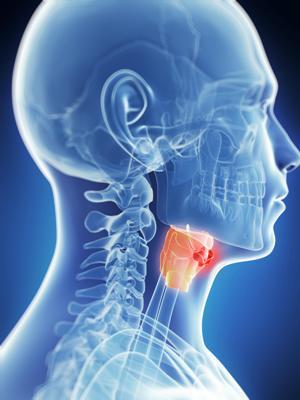

Опухоль гортани может быть доброкачественной или злокачественной. Важно знать симптомы для своевременного обращения к врачу и начала лечения. Рассмотрим основные проявления опухолей гортани, их отличия, методы диагностики и современные подходы к лечению. Эта информация поможет читателям лучше понять свое состояние и принять обоснованные решения о лечении.

Рак горла представляет собой сложное понятие, охватывающее различные образования как в горле, так и в глотке. Причины возникновения этого заболевания могут быть разнообразными. К основным факторам относятся табачный дым и неконтролируемые патологические изменения в клетках.

Для диагностики используются различные методы, включая ларингоскопию и биопсию. Врач может также назначить компьютерную томографию для более детального обследования. Лечение зависит от стадии заболевания и может включать хирургическое вмешательство, радиотерапию или химиотерапию. Важно помнить, что своевременное обращение к врачу и соблюдение рекомендаций специалистов играют ключевую роль в успешном выздоровлении.